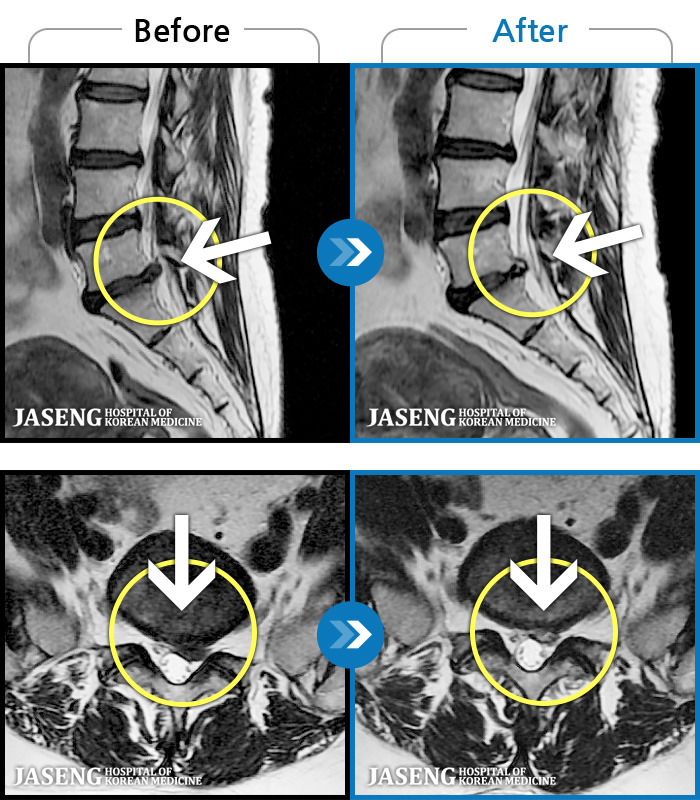

MRI ġ

1,304 MRI ũ ʸ Ȯϼ.